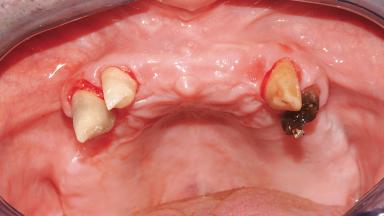

A 63-year-old male patient was referred for a consultation and treatment of partial edentulism in the maxilla. The patient presented with residual anterior teeth and declined a partial removable prosthesis. He reported that the maxillary posterior teeth had been extracted due to mobility and periodontal disease two months before the consultation. The patient’s chief complaint was that his residual maxillary teeth were mobile and that he was unable to chew. The patient’s desire was a stable and comfortable fixed maxillary rehabilitation. The patient was a light smoker (fewer than 10 cigarettes/ day), and his medical history was without significant findings. He was not on any regular medication at the time of consultation. The extraoral examination revealed a normal physiognomy with a correct distribution of the facial thirds. The patient presented a low lip line, and the transition line between teeth and soft tissues was not exposed during a forced smile.